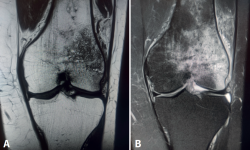

El concepto de edema óseo fue descrito por primera vez por Wilson en 1988(1), como un cuadro clínico doloroso que muestra en la imagen de resonancia magnética (RM) una señal hipointensa en las secuencias T1 e hiperintensa en las T2 (Figura 1), y fue interpretado como un aumento del contenido de agua en la médula ósea. Posteriormente, aparecieron otros términos en la literatura que hacían referencia a imágenes superponibles en RM a las descritas por Wilson, como “síndrome de edema óseo transitorio” u “osteoporosis transitoria”. Actualmente, se considera más correcto emplear el término “lesiones de médula ósea”, que engloba un amplio grupo de condiciones clínicas que comparten el dolor como síntoma principal e imagen similar en la RM, pero con gran variabilidad etiopatogénica e histológica.

Figura 1. Cortes coronales de resonancia magnética de rodilla izquierda con edema óseo de origen traumático. A: en las secuencias potenciadas en T1 el edema óseo presenta una señal hipointensa; B: en las secuencias potenciadas en T2, presenta una señal hiperintensa.